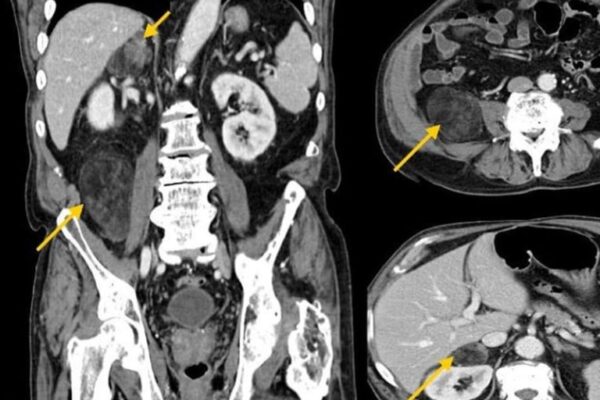

- Bilgisayarlı Tomografi

- Dual Enerji BT